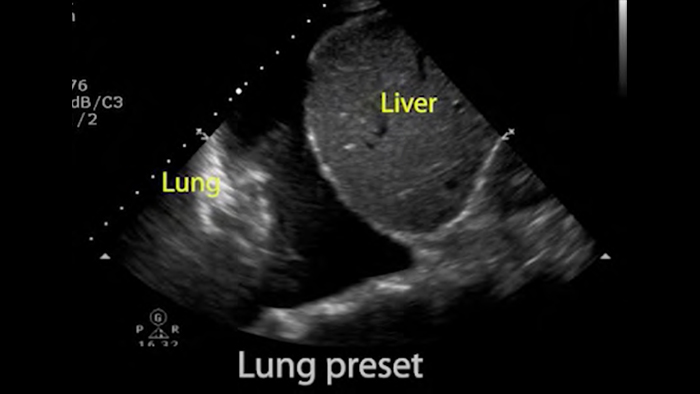

System Lumify do badań POCUS może służyć do wykrywania rurki dotchawiczej w tchawicy, pomagać podczas pilnych zabiegów konikotomii, diagnostyce wysięku opłucnowego oraz chorób pęcherzyków płucnych.

Podstawy ultrasonografii płuc